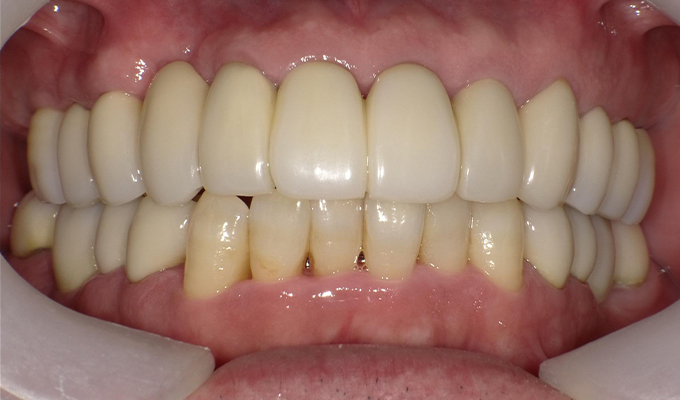

case5インプラント+メタルボンドブリッジ

初診時(2010年)

初回メンテナンス時(2012年)

最新メンテナンス時(2023年)

- 初診時の年齢

- 40代女性 (2010年)

- 主訴

- 5年ほど前に上に総入れ歯を作った。(マグネットタイプ)食事してたら人口歯が取れてしまった。インプラントに興味がある。40代なので入れ歯はやっぱり嫌、とのことでした。

- 治療内容

- 上・・・虫歯の根だけの歯が数本残っているためすべて抜歯し仮義歯作成しました。最終的には8本インプラントを埋入し上部構造はメタルボンドです。

下・・・保存できる下の歯はメタルボンドブリッジにし、奥歯のない部分に3本インプラントを埋入しました。治療期間は2年ほどかかりましたがしっかり食事ができるようになったので嬉しいと、満足していただけました。

以降定期的にメンテナンスに来院いただき11年経過してもいい状態を維持されています。